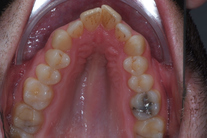

35-årig man med smal och trångställd tandbåge. Vill ha ett jämnt leende. Behandling bestod av knappt 9 månader med genomskinliga Invisalignskenor.